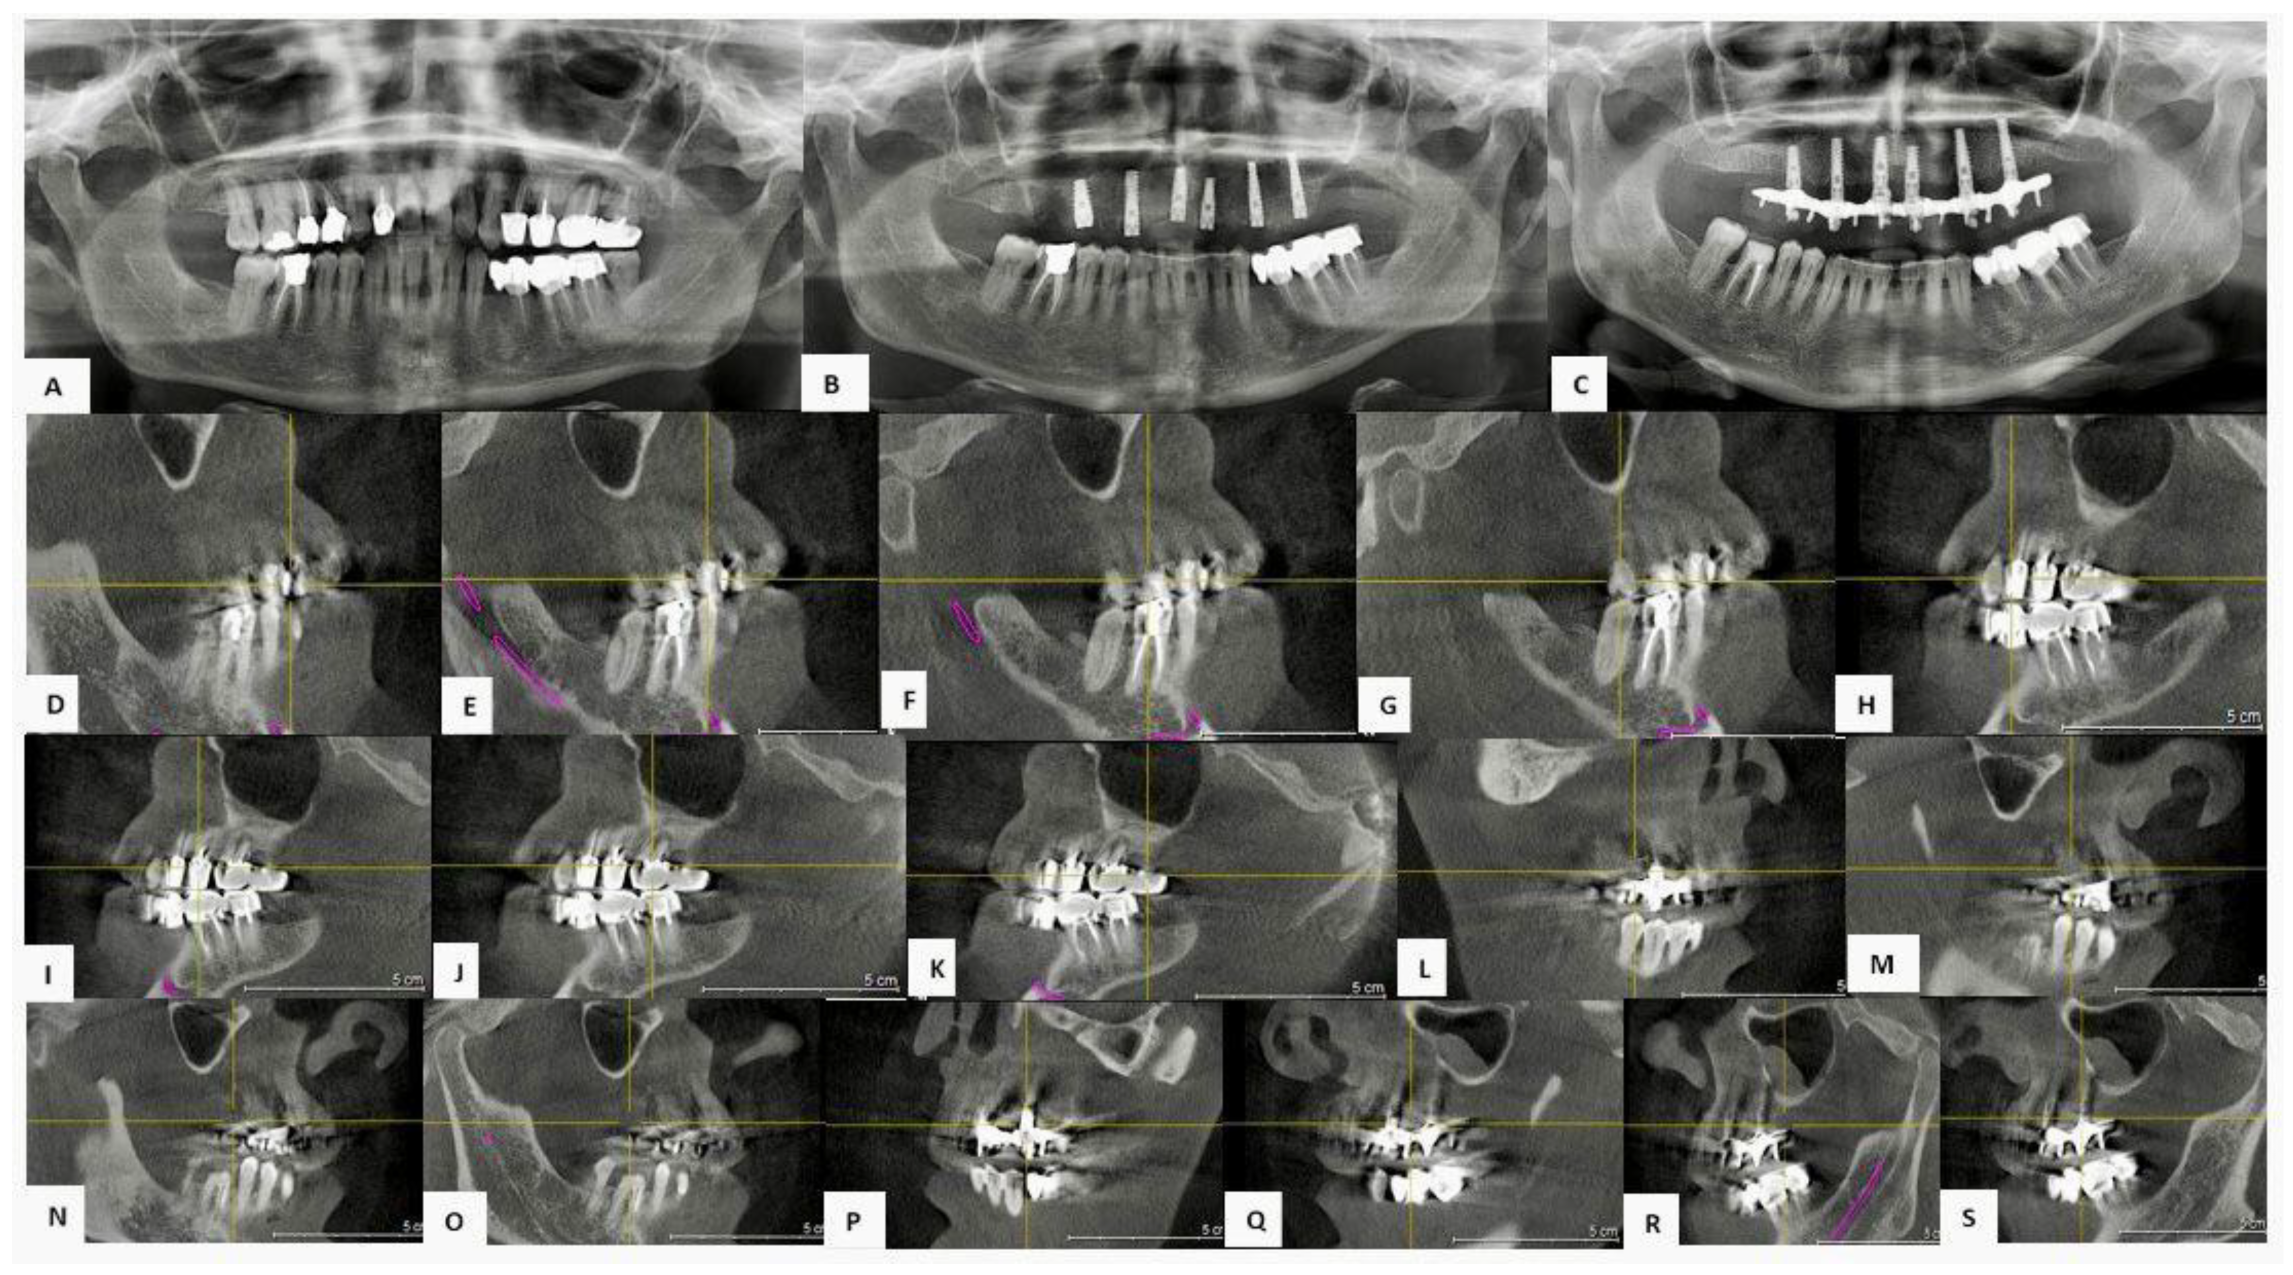

3.3.1. Case 1—Female Patient, 52 Years Old

3.3.2. Case 2—Female Patient, 60 Years Old

3.3.3. Case 3—Male Patient, 58 Years Old

4.2. Considerations on Representative Clinical Cases